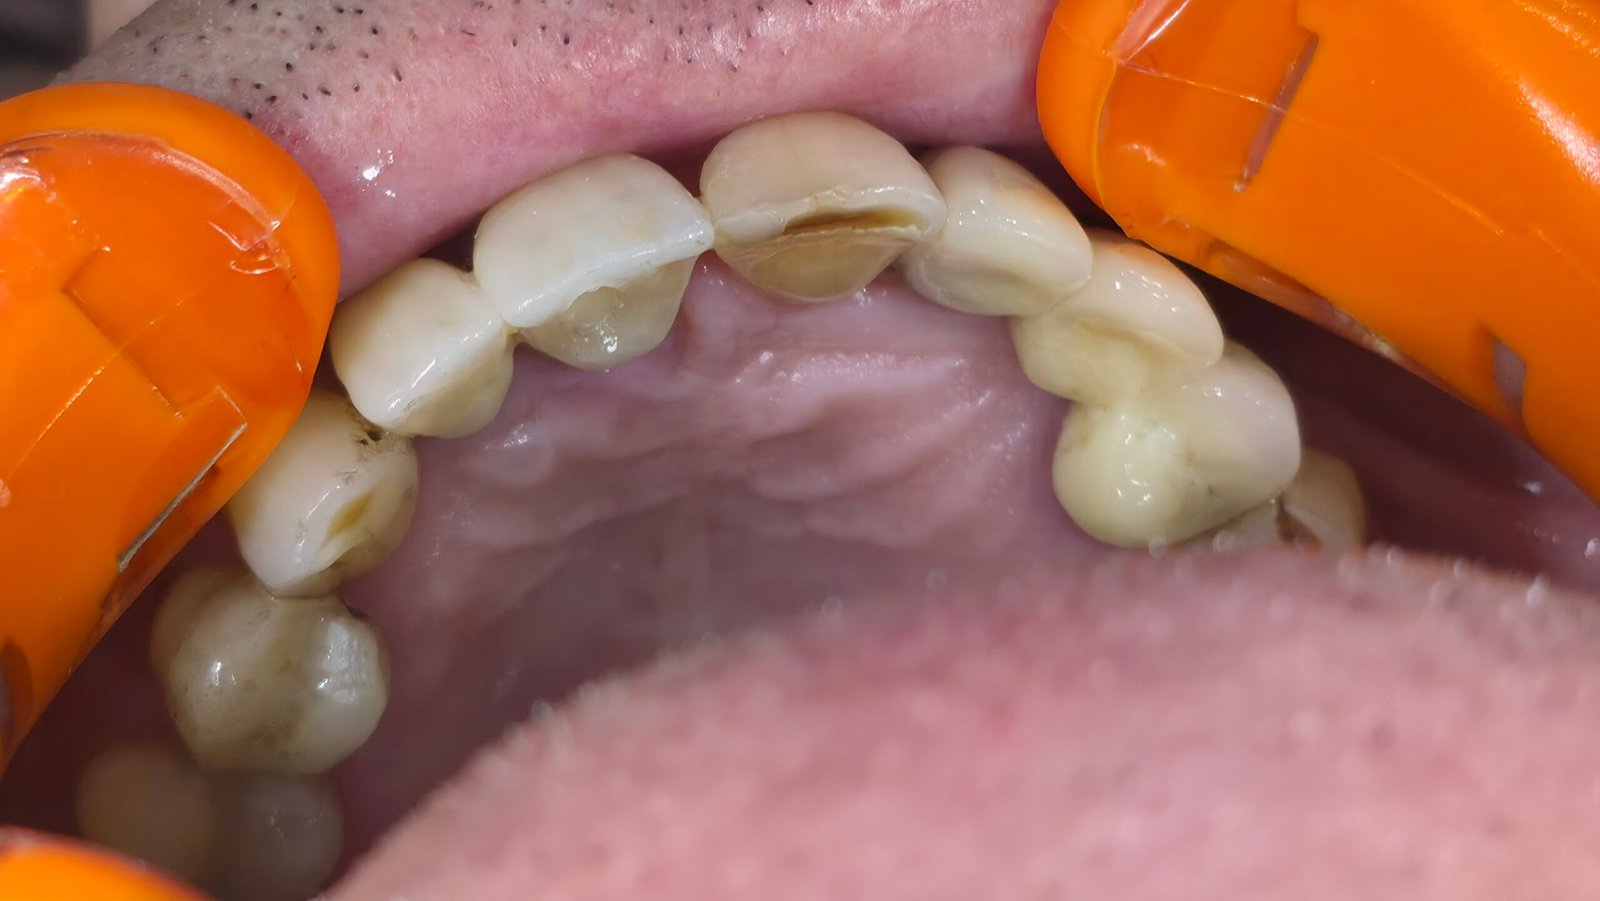

Réhabilitation esthétique après orthodontie : full-zircone & disilicate de lithium

Une jeune patiente arrive en fin de traitement orthodontique pour un déficit esthétique.

La difficulté réside dans la réalisation de prothèses différentes dans le même secteur : jongler avec la full-zircone et le disilicate de lithium.

Ce challenge fut le sujet de mon mémoire du DU d’esthétique de Strasbourg en 2008.

L’expérience et l’investissement dans le digital depuis 2017 rendent le résultat plus prévisible.